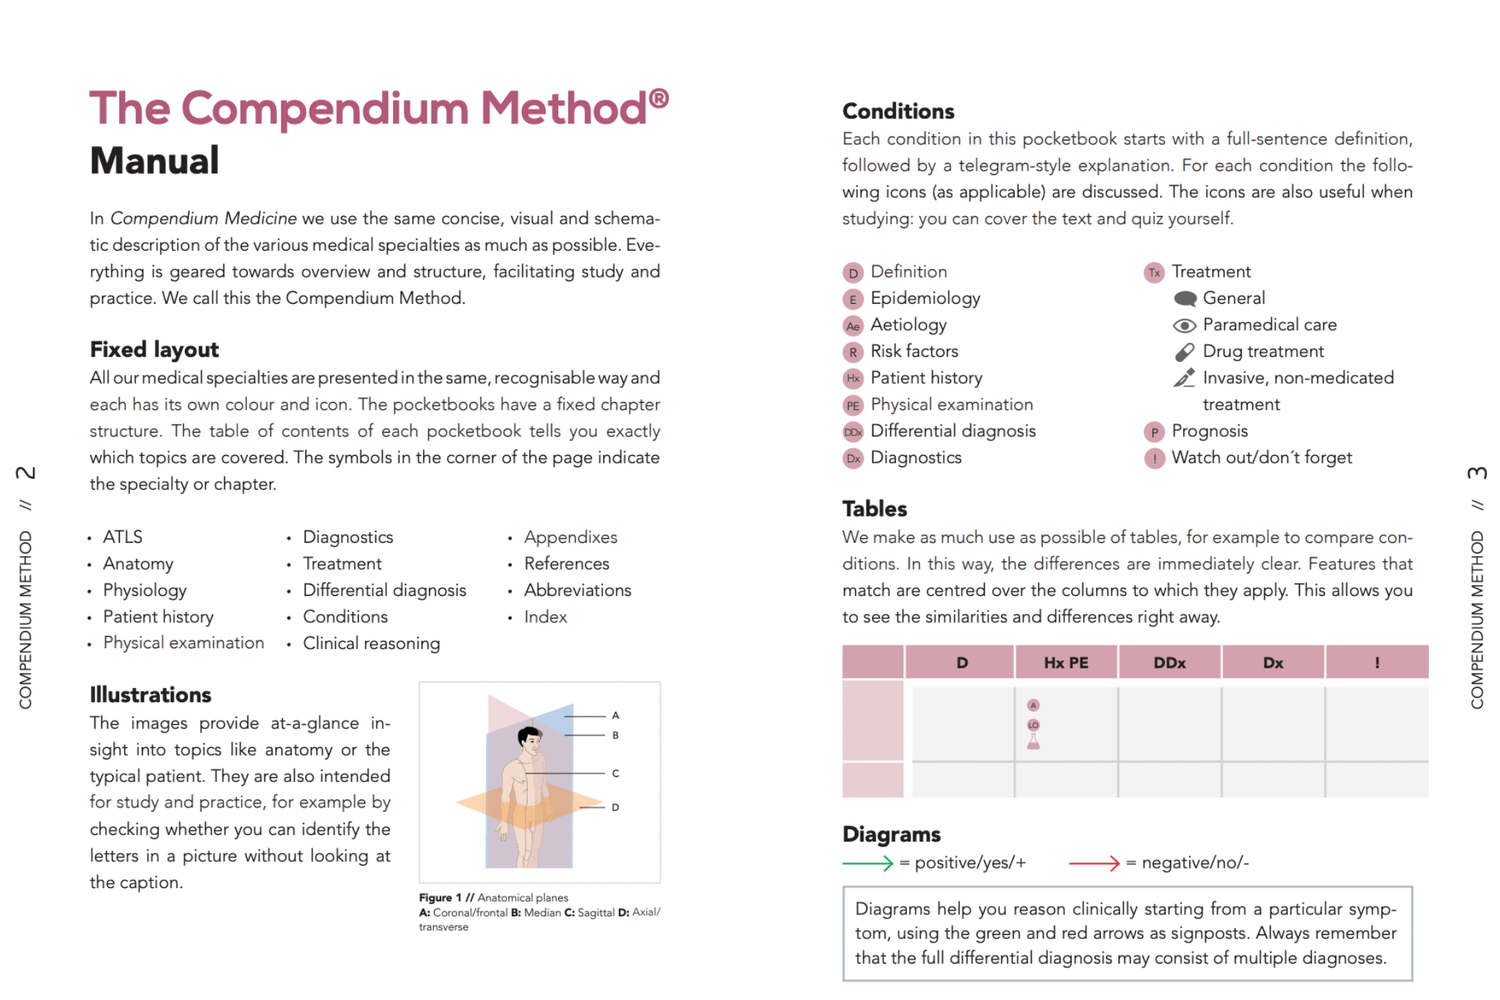

The Compendium Method© simplifies radiology with structured layouts, clear visuals, and diagrams – helping you understand and apply knowledge more effectively, even under pressure.